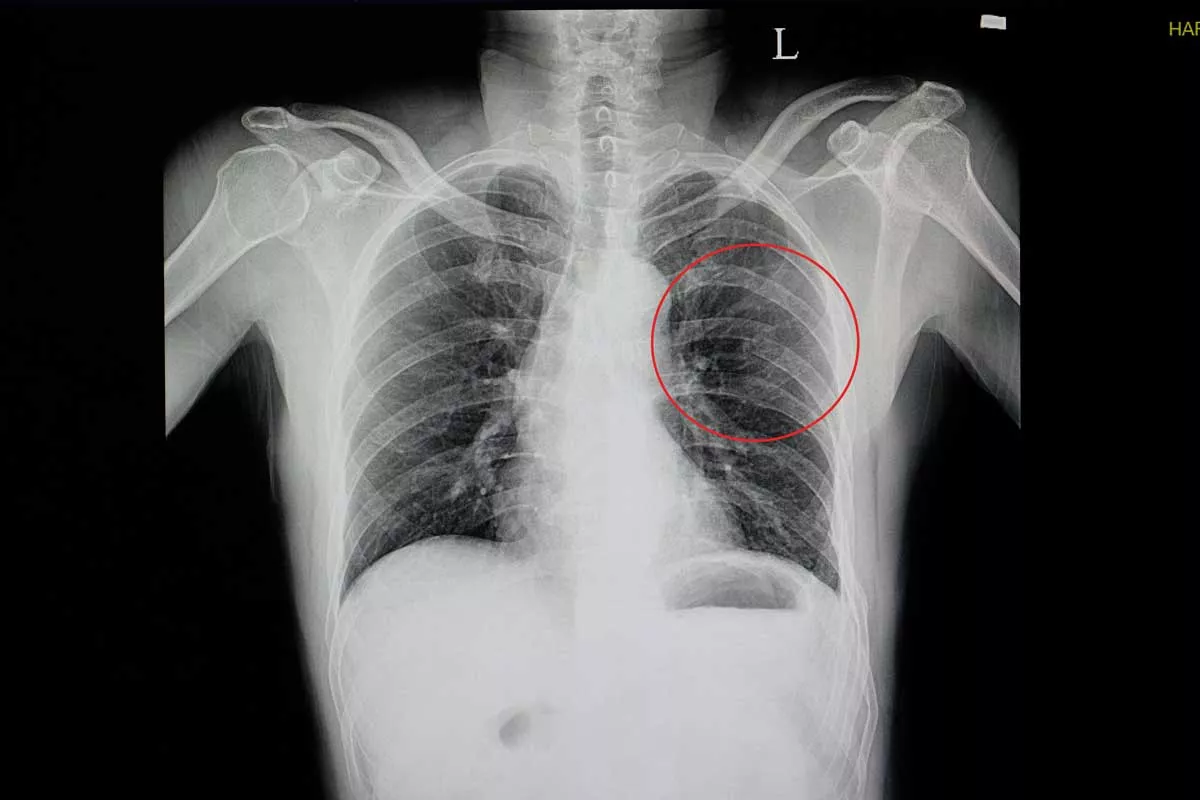

In some cases, injured individuals may experience shortness of breath or difficulty breathing. This can indicate a potentially life-threatening situation that needs immediate medical intervention.